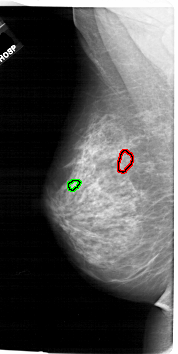

A_1744_1.LEFT_MLO

LEFT_MLO LINES 6721 PIXELS_PER_LINE 3376 BITS_PER_PIXEL 12 RESOLUTION 43.5 OVERLAY

FILE: A_1744_1.LEFT_MLO.OVERLAY

TOTAL_ABNORMALITIES 1

ABNORMALITY 1

LESION_TYPE CALCIFICATION TYPE PLEOMORPHIC DISTRIBUTION CLUSTERED

ASSESSMENT 4

SUBTLETY 2

PATHOLOGY BENIGN

TOTAL_OUTLINES 1

BOUNDARY

ABNORMALITY 2